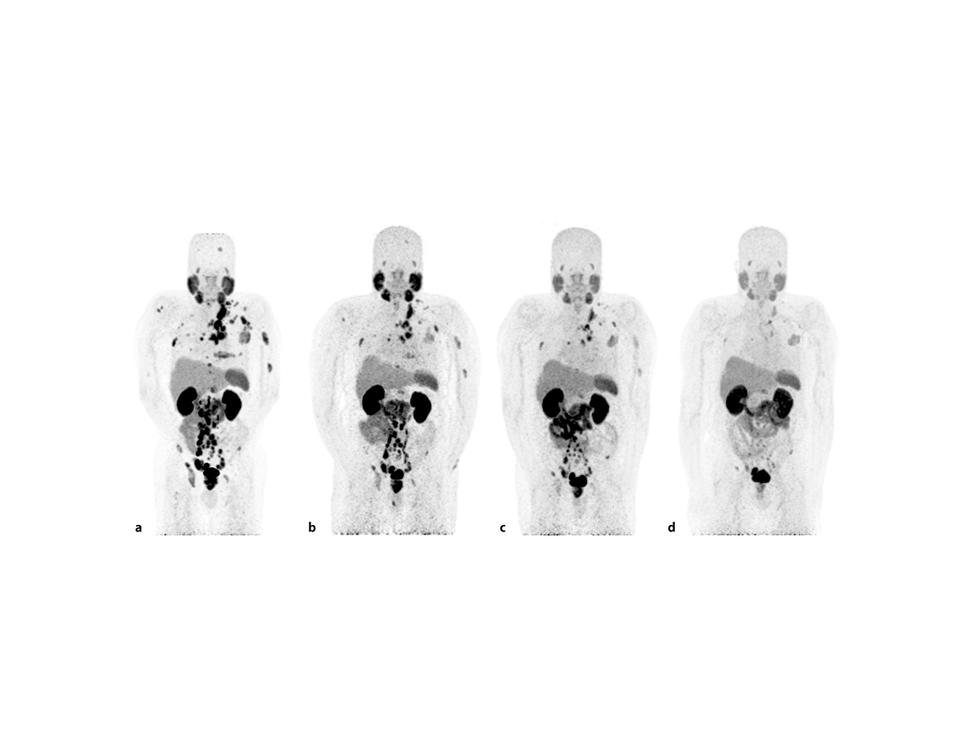

图片来源:National Cancer Institute(NCI),PSMA PET 扫描可在传统骨扫描之前发现更微小的前列腺癌转移灶,这也是美国前列腺癌晚期治疗中越来越核心的影像工具。

从临床策略上看,美国目前最大的优势之一,是将PSMA PET分子影像提前用于治疗决策,而不仅仅用于复发确认。2026年U.S. Food and Drug Administration批准的新一代 Pylarify TruVu 成像系统,使PSMA扫描产能提高约50%,这意味着更多患者能在更早阶段发现微小转移灶,而不是等到传统骨扫描已经出现明显病灶时才调整方案。

这也是为什么很多晚期患者在比较“国内方案是否已经足够”时,会特别关注国外治疗前列腺癌成功案例——因为在某些病例里,治疗差异并不来自药物本身,而来自“发现得更早,切换得更快”。